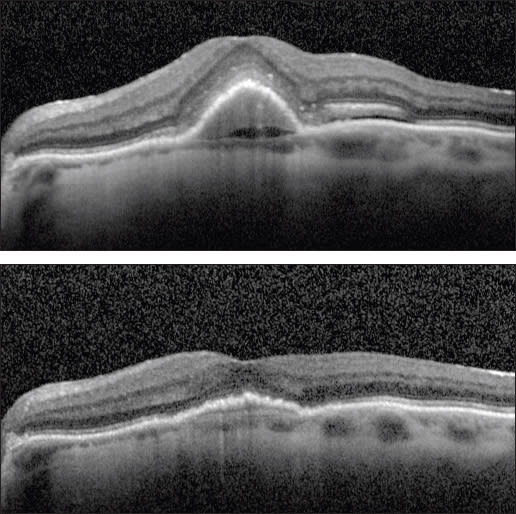

Figure 1. (top) A patient with a new occult CNV with PED and subretinal fluid was treated with two monthly intravitreal injections of ranibizumab with flattening of the PED and resolution of the SRF (bottom).

Case 1. This case involved a 92-year-old woman who presented with a new occult lesion in the left eye. Prior to her conversion, her baseline vision was 20/40. Despite new CNV with a PED and subretinal fluid noted on OCT, her vision remained unchanged (Figure 1). She was treated twice with intravitreal ranibizumab with dramatic resolution of the PED and subretinal fluid.